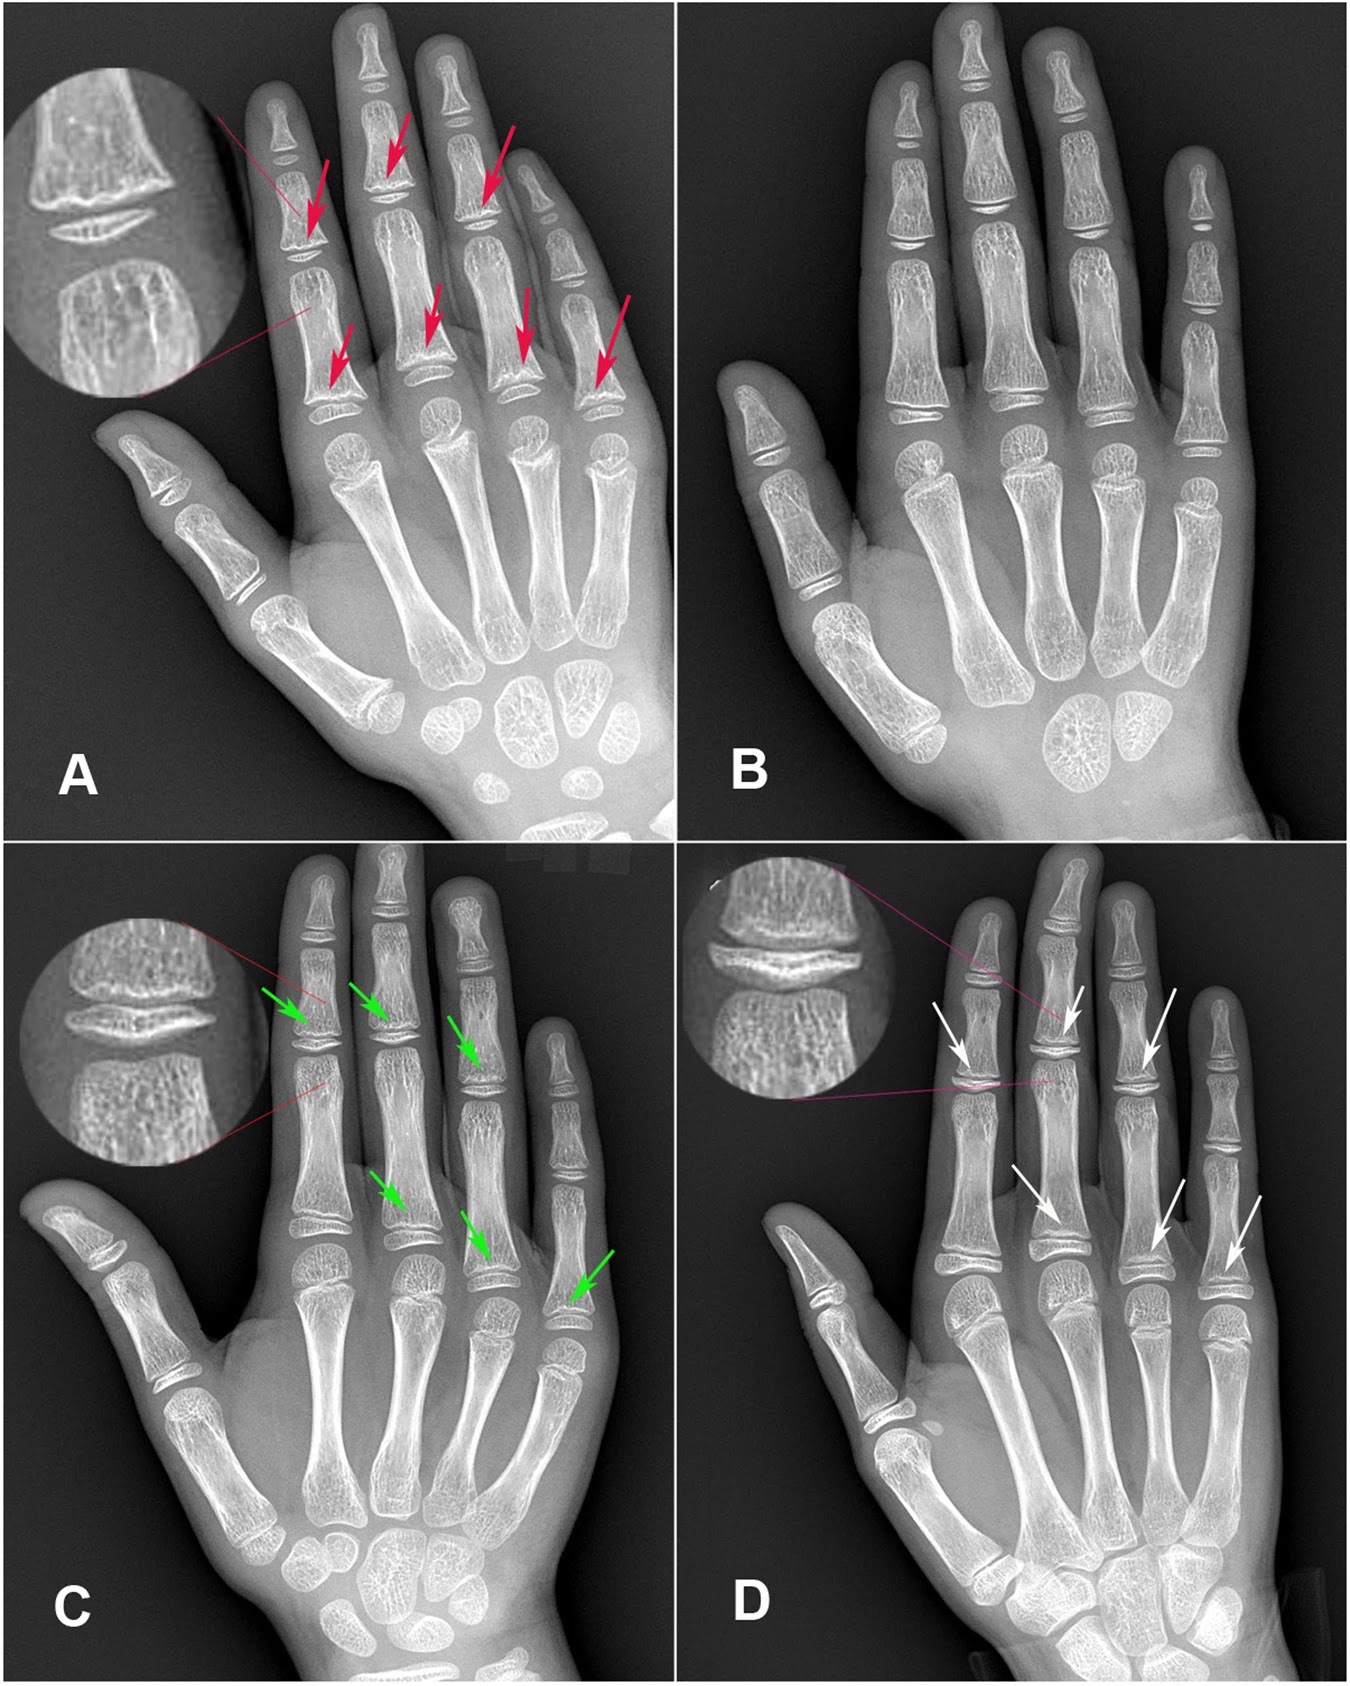

(A) Is a radiological image of the right hand with KBD-positive X-ray signs in an 8-year-old boy: some metaphyseal hardening signs, waviness or serration changes and small depressions (red arrows) are found in the zones of provisional metaphyseal calcification in the fingers (including index finger, middle finger and ring finger).

(B) Is a radiological image of the right hand of a 7-year-old healthy boy: all metaphyses, epiphyses and diaphyses were glabrate, uniform, sinuous and non-destructive. The carpals were not completely formed.

(C) Is a radiological image of the right hand of an 11-year-old girl with CRME in the equal-diameter period: the diameter of metaphysis and epiphysis are almost equal. Although it belongs to the normal development periods before complete closure of metaphysis-epiphysis (CCME), its imaging signs are similar to KBD-positive X-ray signs. Index finger, middle finger, ring finger and little finger show metaphyses serrated, wavy (green arrows).

(D) Is a radiological image of the right hand of a 10-year-old girl with CRME in the ultra-diameter period: The diameter of epiphysis is longer than that of metaphysis. It occurs after the equal-diameter period normally and the features are similar to KBD-positive X-ray signs. Some metaphyseal waviness, serration and irregularly depressions are found in many fingers (white arrows).